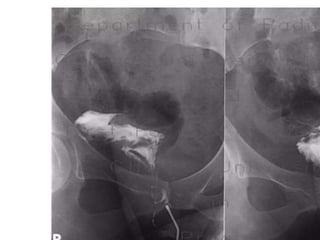

Tracheo-oesophageal fistula

Rectovaginal fistula

• 57.

• 59.